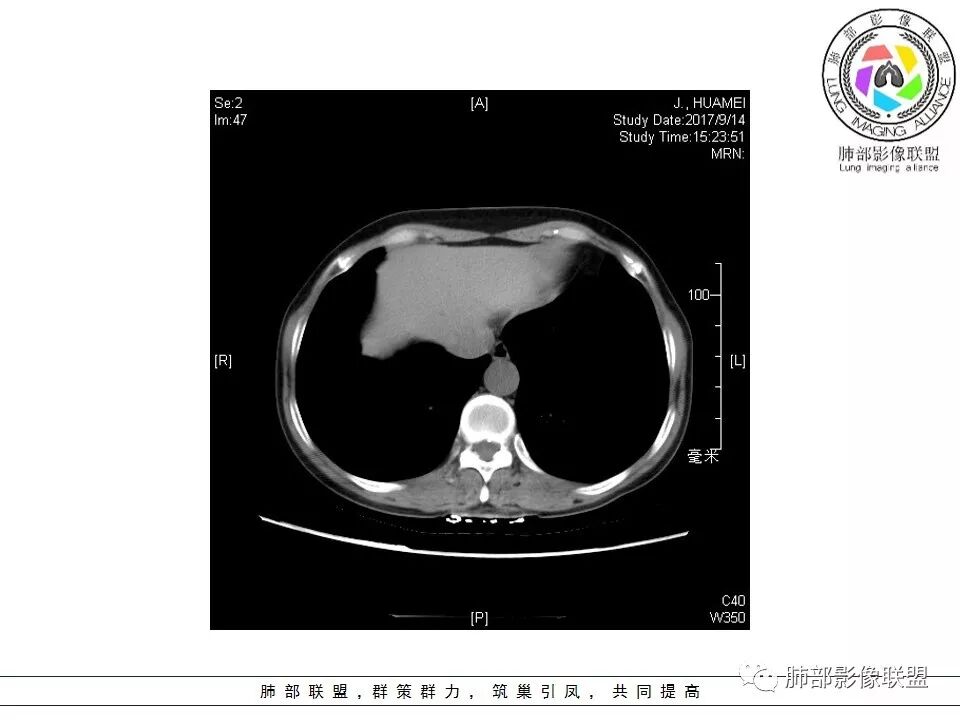

晨读:右肺下叶肿块影,浅分叶,不均匀强化,有血管穿行其中,考虑肺癌,神经内分泌肿瘤可能性大。

右肺下叶结节,边缘毛糙,内支气管推移,有血管贴行,小细胞肺癌?

晨读:右下肺前基底段支气管亚段分叉处占位,密度均匀、中度均匀强化,结节近边缘有支气管、血管穿行,结节边缘较光滑、有细短毛刺、无分叶,结节周围无卫星灶。考虑:PSP,鉴别:小细胞肺癌、不典型错钩瘤

内部支气管扩张,穿行血管形态自然,支持malt。

轻度分叶,支气管穿行,轻中度强化,血管漂浮,考虑MALT

右肺下叶前基底段肿块,边缘不光滑,毛糙,内见充气支气管征,边缘有浅分叶,肿块周围无病灶,排除了结核。增强扫描明显强化,内见血管影,考虑恶性肿瘤。女性,腺癌多见。

淋巴瘤与小细胞癌鉴别,纵隔内没有肿大淋巴结、结节边缘比较毛糙,淋巴瘤放第一位。

病灶呈圆形,轻度分叶,内见血管及支气管影,考虑MALT。

右肺下叶前基底段结节 边缘磨玻璃密度较清 内部支气管扩张,轻中度强化 穿行血管形态自然,支持淋巴瘤。

晨读:右肺下叶肿块影,浅分叶,边界清,轻度均匀强化,血管自然穿行,NSE偏高,考虑小细胞肺癌!

中年女性,右肺下叶前基底段肿块,轻度分叶,有棘样突出,充气支气管征穿行并形成脐凹征。增强扫描中度强化,内见血管影,血管壁毛糙,考虑恶性,腺癌?小细胞肺癌?

晨读,右肺下叶前基底段实性结节,边缘膨隆,可见多发浅分叶,结节内密度均匀,增强后呈轻度均匀强化,血管穿行走形自然,首先考虑恶性肿瘤,内有支气管穿行,淋巴瘤可能大,腺癌待排。

右肺下叶肿块,边缘光滑,浅分叶,膨隆明显,局部有清楚的ggo,考虑恶性,类癌首可能,鉴别腺,PSP。

中年女性,右下类圆形肿块,部分膨胧,边缘浅分叶,脐凹,内见血管穿行,增强轻中度强化,叶间胸膜结节?考虑腺癌,内有支气管穿行,鉴别淋巴瘤。

右肺下叶肿块影,边缘光滑,彭隆,浅分叶,内见支气管通过,增强明显强化,内见血管影,考虑恶性肿瘤,神经内分泌癌,鉴别淋巴瘤。

中年女性,体检发现,病史及化验无特殊。胸部CT右肺下叶前基底段见一类圆形结节,边界清楚,分叶不明显,边缘呈锯齿状改变,病灶内支气管穿行,无扩张及扭曲,增强扫描病灶明显均匀强化,内见穿行血管影,走形无扭曲。考虑粘膜相关性淋巴瘤可能。鉴别炎性假瘤、腺癌及小细胞癌。

胸CT:右肺下叶前基底段占位性病变,内可见支气管穿过,病灶边缘不规则,呈浅分叶,未见明显毛刺。纵隔窗可见病灶密度相对均匀,增强可见病灶强化,内可见血管增粗,边缘模糊,总体考虑恶性,腺?。良性疾病鉴别错构。

右下肺类圆形实形结节,边缘膨隆,浅分叶,其内可见支气管及血管影走行,轻度强化,考虑恶性病灶,淋巴瘤?类癌?

边缘彭隆,还是考虑肿瘤,支气管通入,肺内原发,支气管自然穿行稍扩张,血管比较自然同行,漂浮征,增强后整个比较均匀无明显坏死,淋巴瘤首选。恶性应该没有问题,建议穿刺。

这个病灶边缘还是有一点点恶性征象,有分叶,似乎有点地方还有一些小毛刺样感觉

部分区域整体以膨隆为主,部分区域稍收缩

内部支气管走形非常自然,达远端稍扩张;内部血管穿行也非常自然

内部密度比较均匀,我们一般来说,首先良性肿瘤不支持,因为它里面的血管走形太自然了;然后就是炎性病变跟恶性肿瘤,但是它的边缘膨隆比较厉害,有些地方还毛刺,不是很清楚,倾向一个恶性病变

恶性的血管穿行自然,包括支气管稍扩张,最常见还是淋巴瘤,它强化比较均匀;

粘液腺癌一般支气管扩张比较罕见,这个密度及强化太均匀,不是很符合,所以把淋巴瘤放前面,癌待排;

方向定在恶性的,炎性病变不是很符合